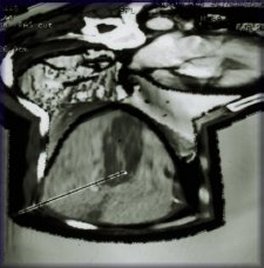

CT scan of the liver before ablation shows large solitary lesion from colorectal carcinoma.

This colon cancer metastasis to the liver had been previously treated with surgery and cryotherapy but had recurred and failed chemotherapy.